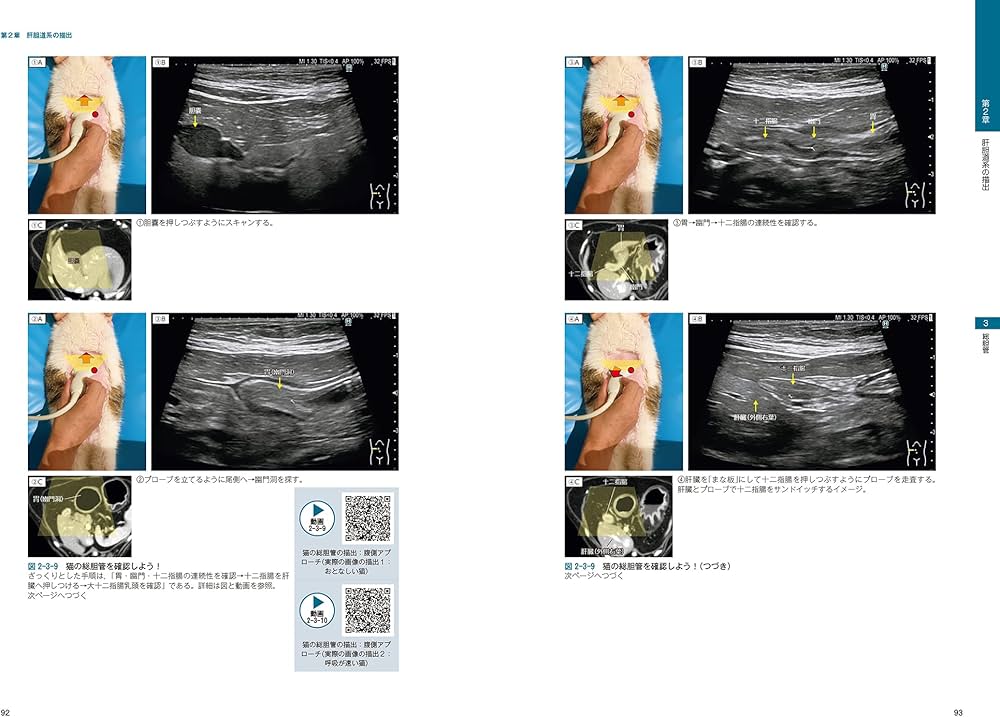

※裁断済みです。自炊にしか使用していませんが、猫を飼育している環境での使用と、裁断済みのため〈状態が悪い〉に設定しております。犬と猫の腹部超音波に関するビジュアルガイド、114ページの詳細な解説付き。- タイトル: 犬と猫の腹部超音波の描出レッスン 下巻- 著者: 戸島鷹史- ジャンル: 健康・医学- 内容: 腹部超音波に関するビジュアルガイド- ページ数: 114ページ- 付属情報: 動画リンク付き- 形式: 書籍ご覧いただきありがとうございます。即購入可です。値引きは基本的には考えておりません。